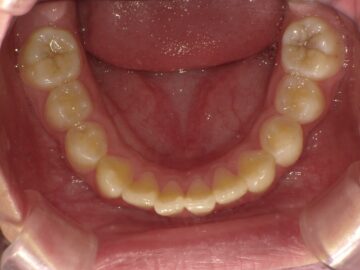

急速拡大装置で上顎の拡大が進むと、下顎の骨も調整する必要が出てきます。その際に使う装置がリンガルアーチです。下顎の骨は上顎の骨と作りが違います。下顎はひとつの骨で構成されているので、上顎と同じように拡大させることができません。内側に傾いている歯を起こすようにして歯列部分だけを拡げていきます。この装置も固定式の装置となっており、歯の裏側に装着しますので目立たない見た目となっています。